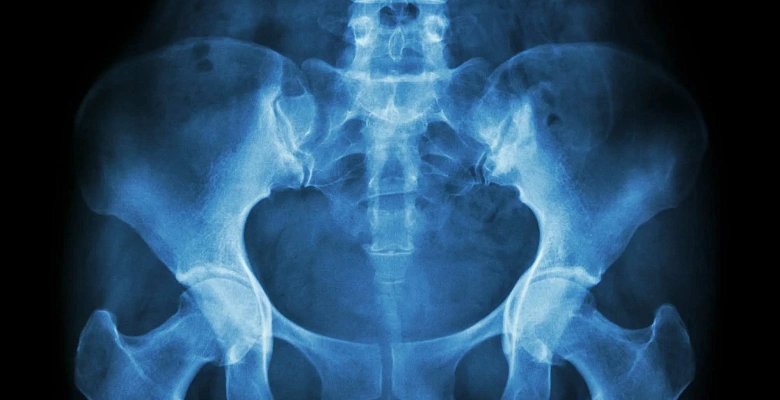

Прямая переднезадняя проекция. Пациент лежит на спине, ноги вытянуты. Позволяет оценить состояние всех костей таза, крестца и тазобедренных суставов.

Боковая проекция. Используется для детального изучения структуры тазовых костей и их взаимного расположения. Часто назначается при подозрении на переломы крестца или копчика.

Косая проекция (по Джудету). Применяется для оценки вертлужной впадины и головки бедренной кости. Используется при диагностике вывихов и подвывихов тазобедренного сустава.